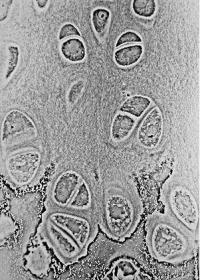

Trong tế bào có những sợi nhiễm sắc thể (chromosome) như những sợi dây quấn mà cuối đầu dây có các phần nhỏ gọi là telomeres, tương tự như dây buộc giày có hai đầu nhỏ cứng để xỏ vào lỗ. Mỗi lần tế bào sinh sản (bằng cách tách đôi) thì các telomeres ngắn đi. Telomeres có nhiệm vụ làm cho tế bào sinh sản, khi telomeres ngắn dần thì khả năng sinh sản cũng từ từ biến mất. Khi tế bào không thể sinh sản để giúp cơ thể thì nó tự hủy (apoptosis).

*Apoptosis increasing from normal cells (top) to apoptotic ones (bottom)

Nhiều tế bào chết thì cơ thể càng già yếu dần. Cuộc nghiên cứu chia hai nhóm người có telomeres dài và ngắn. Người có telomeres dài thì sống 5 năm lâu hơn người có ngắn telomeres.